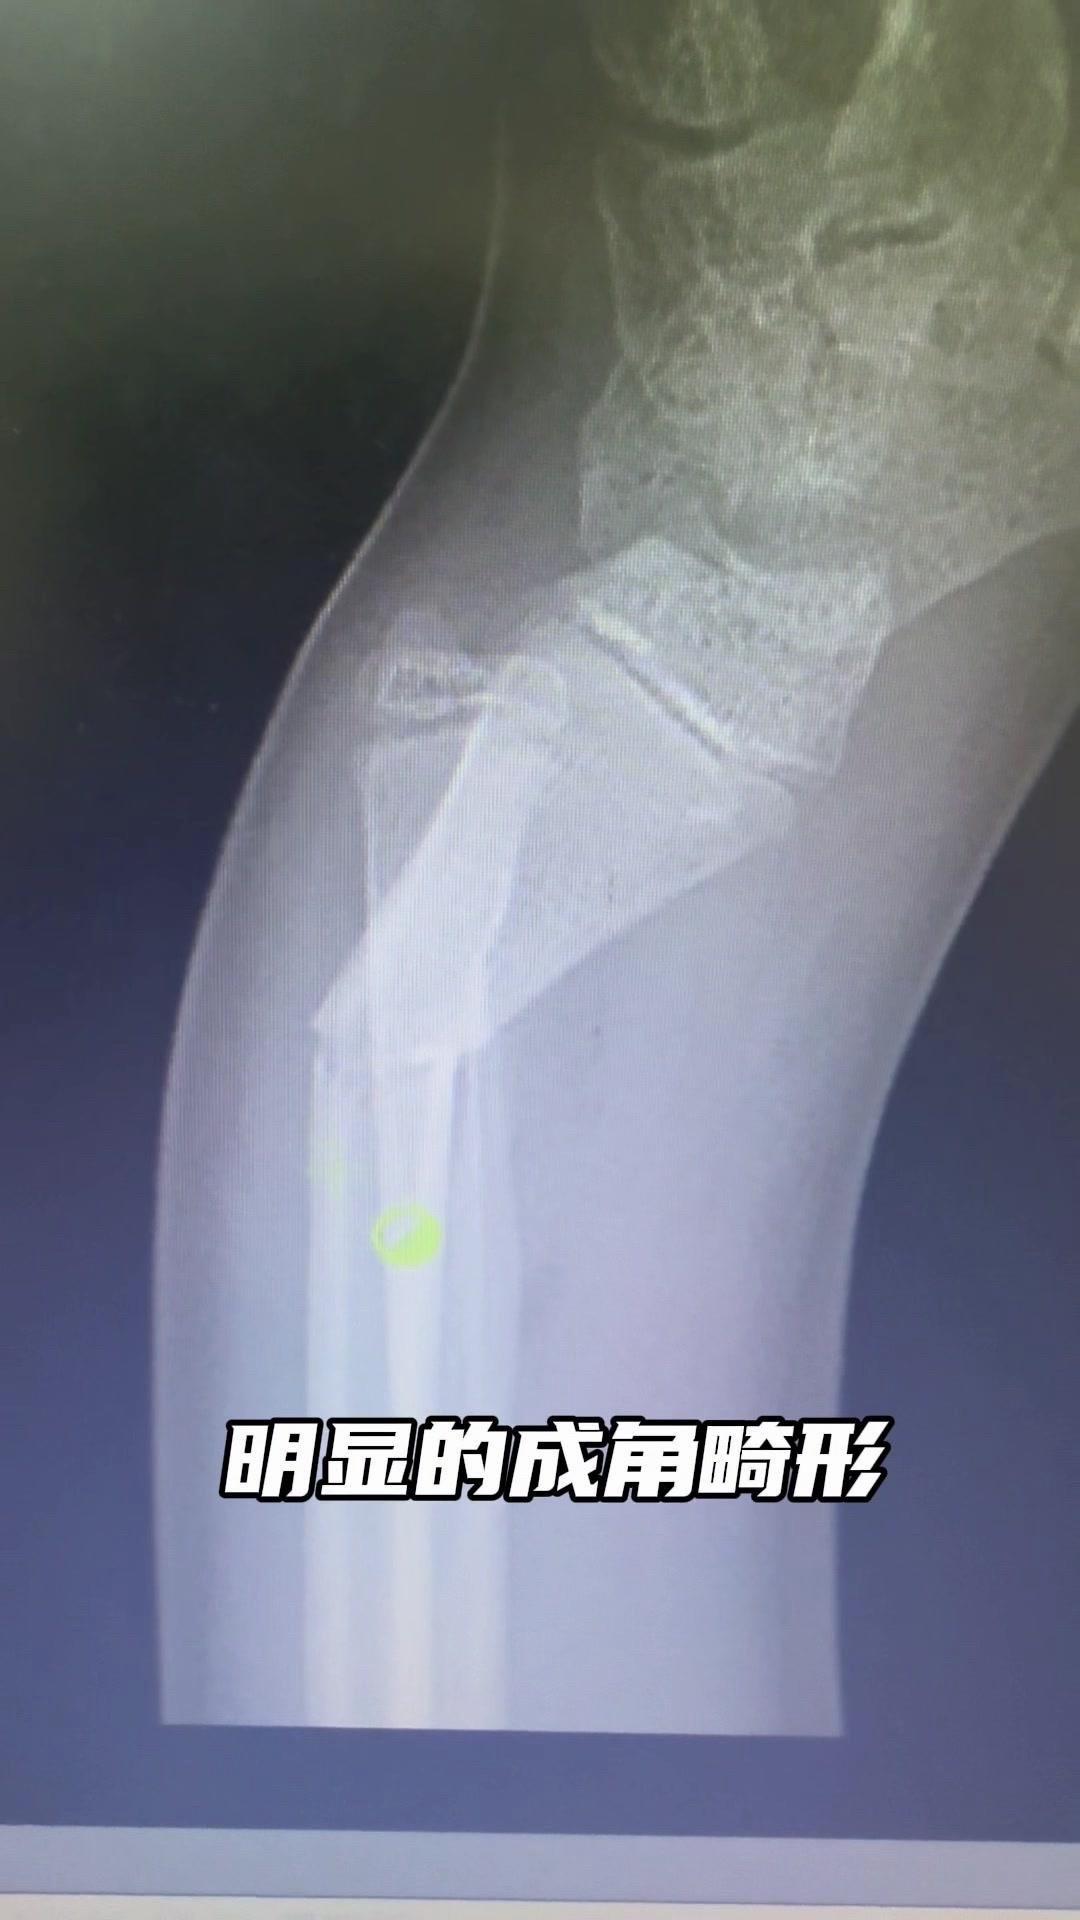

儿童骨折别拖延!💡上周接诊一个10岁女孩,摔了一跤后腕部疼痛还伴有畸形,家长觉得是小伤没在意,结果一周后孩子疼得更厉害,畸形也更明显了。来医院拍片一看,妥妥的骨折,而且才一周就开始出现模糊骨痂,掌区还有45度左右的成角畸形。家长这才意识到问题严重性,其实孩子受伤后出现疼痛、畸形,哪怕看起来不严重,也得及时检查,别让小问题拖成大麻烦。